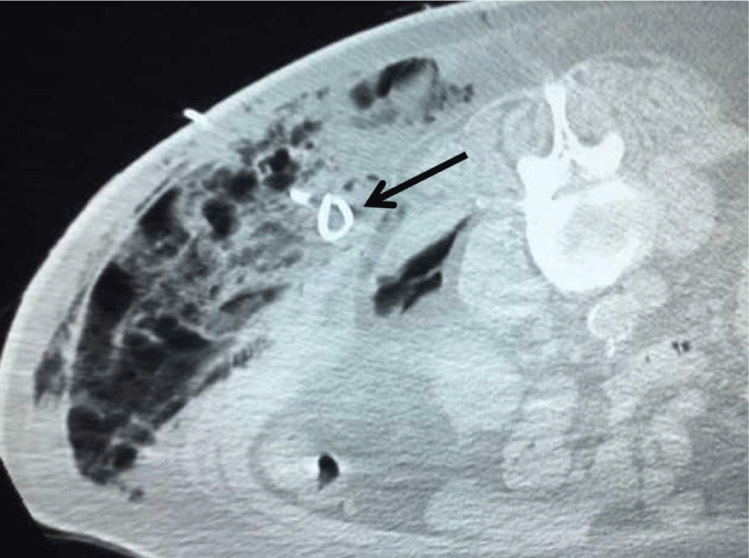

The patient is a 71 year old man with a history of a gastrointestinal stromal tumor (GIST) with s/ p tumor resection approximately three years prior to his presentation. A routine surveillance CT scan for his GIST tumor demonstrated a solid 1.8 cm exophytic left renal mass (Figure 1). After consultation with an urologist, the patient was scheduled for microwave ablation of the renal mass.

Figure 1: Axial CT scan of abdomen in a prone position shows an exophytic solid lesion (arrow; 1.7 cm in diameter, 46 Hounsfield units) arising from the left kidney.